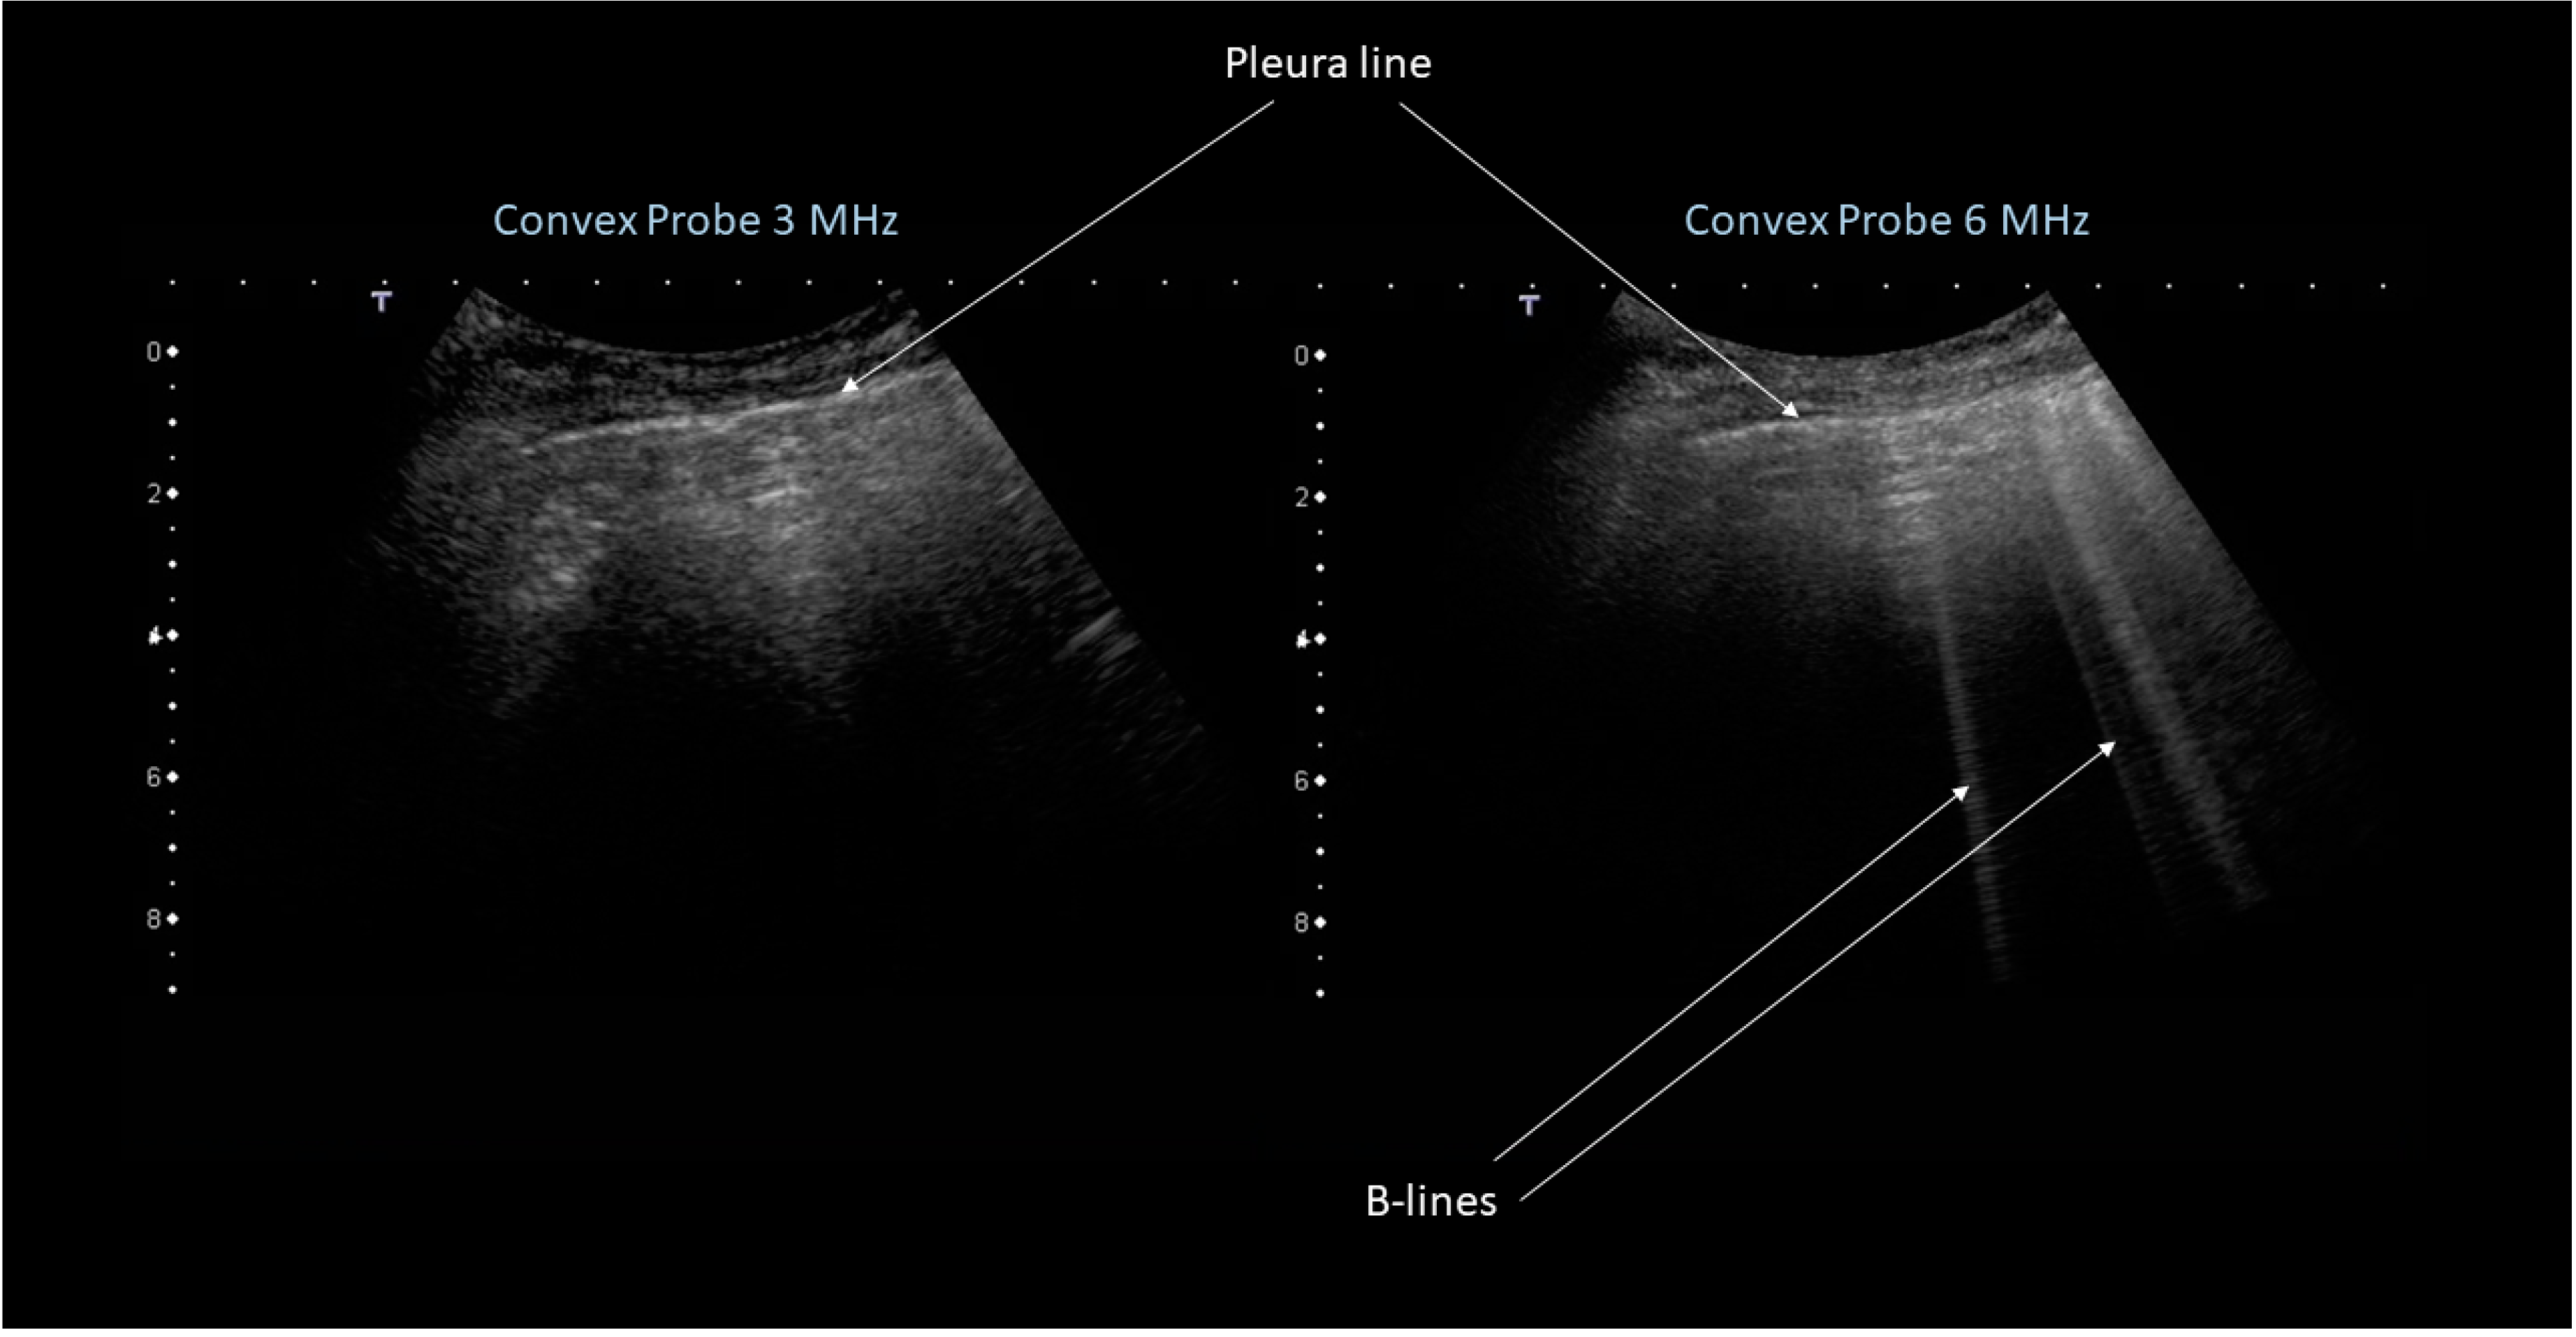

- Volpicelli, G.; Elbarbary, M.; Blaivas, M.; Lichtenstein, D.A.; Mathis, G.; Kirkpatrick, A.W.; Melniker, L.; Gargani, L.; Noble, V.E.; Via, G.; et al. International Liaison Committee on Lung Ultrasound (ILC-LUS) for the International Consensus Conference on Lung Ultrasound (ICC-LUS). International evidence-based recommendations for point-of-care lung ultrasound. Intensive Care Med. 2012, 38, 577–591. [Google Scholar] [CrossRef]

- Lichtenstein, D.A. Lung ultrasound in the critically ill. Ann. Intensive Care 2014, 4, 1. [Google Scholar] [CrossRef]

- Soldati, G.; Demi, M.; Inchingolo, R.; Smargiassi, A.; Demi, L. On the physical basis of pulmonary sonographic interstitial syndrome. J. Ultrasound Med. 2016, 35, 2075–2086. [Google Scholar] [CrossRef] [PubMed]

- Soldati, G.; Demi, M.; Smargiassi, A.; Inchingolo, R.; Demi, L. The role of ultrasound lung artefacts in thediagnosis of respiratory diseases. Expert Rev. Respir. Med. 2019, 13, 162–172. [Google Scholar] [CrossRef] [PubMed]